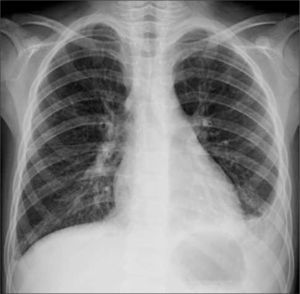

La radiografía (Rx) de tórax se considera como el mejor método diagnóstico en esta patología, de valor tanto desde un punto de vista clínico como epidemiológico (Figura 1) (1,4). Estudios reportan que en los pacientes en que se solicitó una Rx de tórax por sospecha de neumonía se produjeron cambios en el diagnóstico hasta en un 20% de los casos y en el manejo, hasta en un 30% de los casos (1). Cuando se dispone del recurso, la Rx debiera solicitarse en niños con: sospecha de neumonía cuando existe clínica dudosa o ambigua, síndrome febril sin foco, neumonía de curso prolongado, antecedente de neumonías anteriores, neumonía que no responde a tratamiento antibiótico o sospecha de complicaciones (3).

El control radiográfico no debiera ser la regla debiendo reservarse para los casos en que los síntomas son persistentes o recurrentes y pacientes con condiciones clínicas especiales que planteen la posibilidad de una evolución menos favorable, como inmunodeficiencias o fibrosis quística (9). La neumonía redonda constituye una condición en la que se acepta el control rutinario dado que plantea diagnóstico diferencial con patologías congénitas y adquiridas. La resolución de las imágenes de condensación en neumonías bacterianas es más rápida en el niño que en el adulto, habitualmente 7 a 10 días en cuadros no complicados (4) (Figura 2).